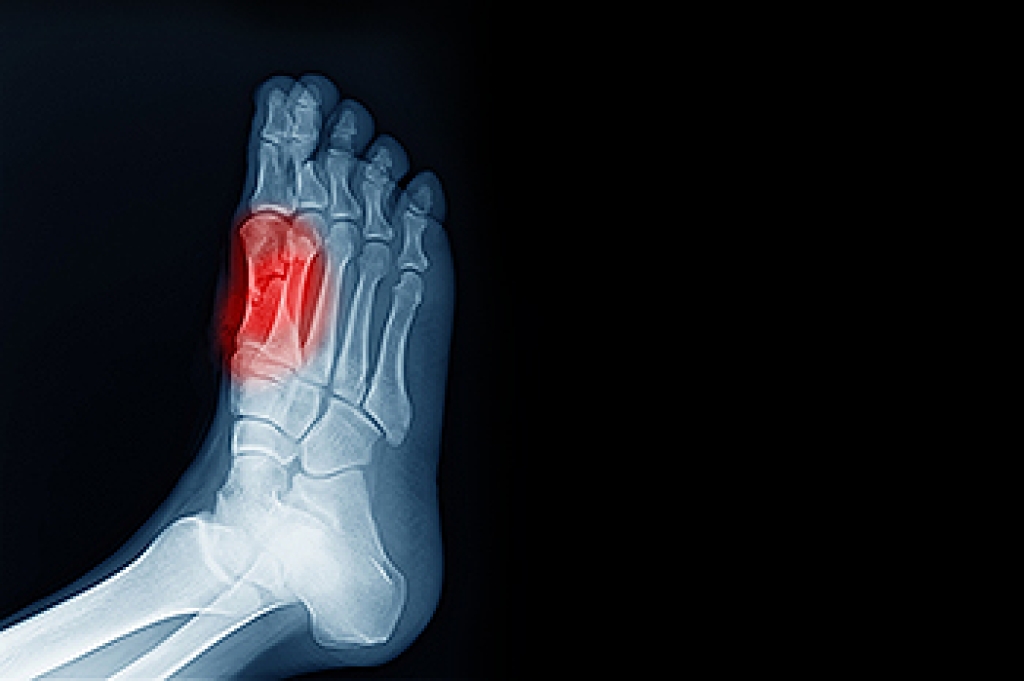

- Broken ankles

- Stress fractures

Due to the wide variety of potential causes of ankle pain, podiatrists will utilize a number of different methods to properly diagnose ankle pain. This can include asking for personal and family medical histories and of any recent injuries. Further diagnosis may include sensation tests, a physical examination, and potentially x-rays or other imaging tests.